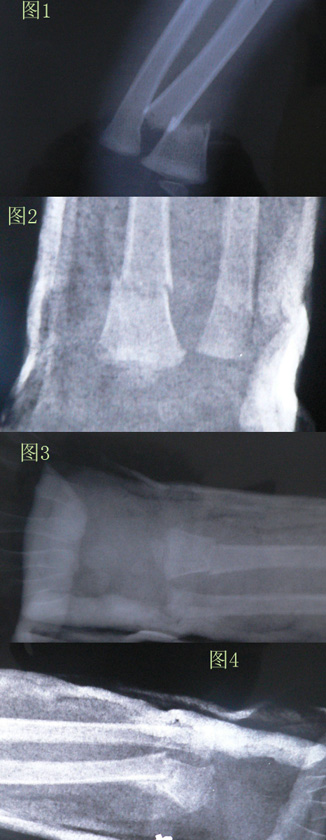

● 详细病情及咨询目的:3周前桡骨远端骨折(图1),完全移位。在306医院复位后效果尚可,咨询了几家医院的医生都说小孩儿恢复能力强,没问题;第二天又去积水潭医院的儿童骨科检查了一下(图2),当然也说没问题;一周后到306复查(图3),医生说没事,让2周后再去复查。今天第三周又去了积水潭医院,片子出来后问题严重(图4):两段骨头对接成很大的角度,而且已经长上了。医生的意思是,如果上周发现问题,还来得及补救,可现在已经长上了,只能下周再去复查,拆石膏,上支具矫正;如果矫正不好,得考虑手术了。

关键问题在最后一张。

来这里咨询一下,帮忙仔细看看最后一张片子,问题真的这么严重吗,有没有塑性好的可能,必须做手术吗?